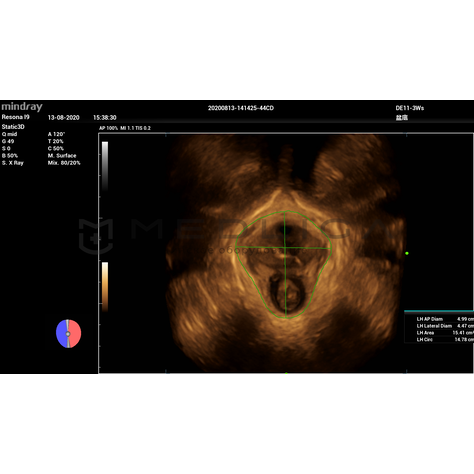

Программное обеспечение для автоматических измерений параметров и оценки функции мышц тазового дна.

Smart Pelvic - новое решение, позволяющее значительно упростить диагностическую процедуру и свести к минимуму время исследования функций мышц тазового дна. Благодаря чрезвычайно простому пользовательскому интерфейсу, программа генерирует стандартную систему координат и автоматически просчитывает все связанные измерения в течение нескольких секунд.